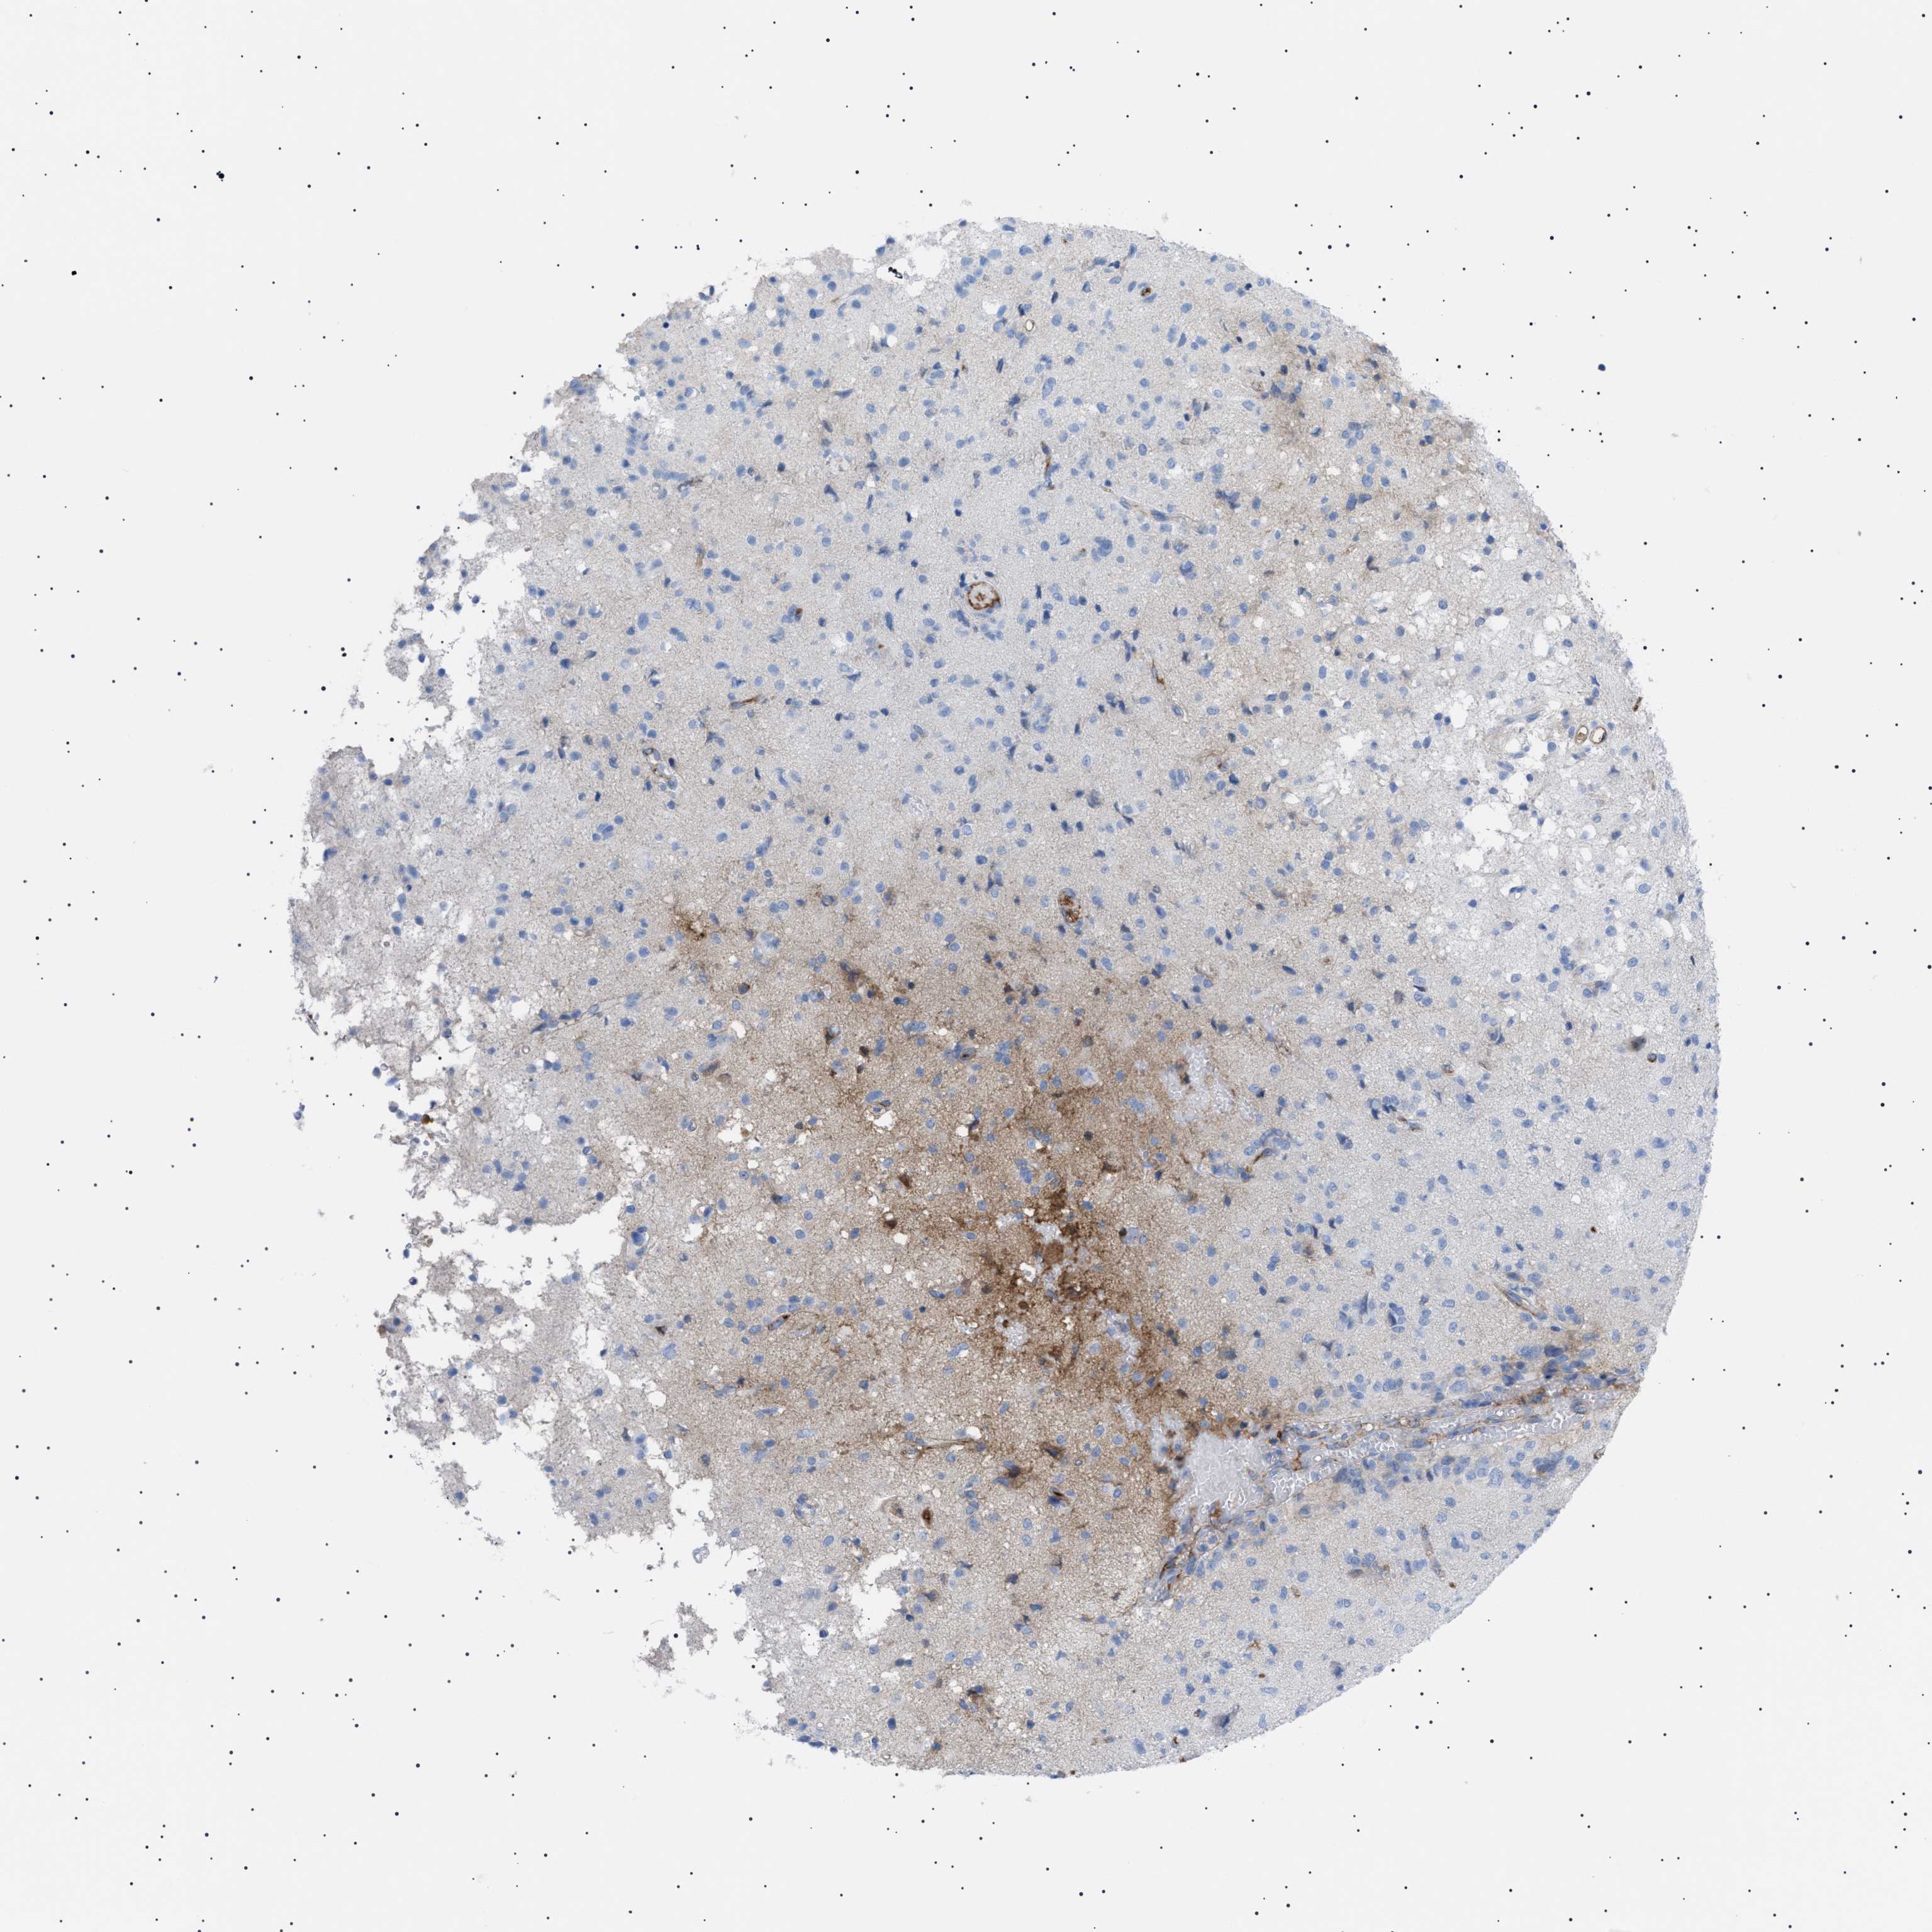

GLIOMA - Protein expressioni

A mouse-over function shows sample information and annotation data. Click on an image to view it in a full screen mode. Samples can be filtered based on level of antibody staining by selecting one or several of the following categories: high, medium, low and not detected. The assay and annotation is described here.

Note that samples used for immunohistochemistry by the Human Protein Atlas do not correspond to samples in the TCGA dataset.

Antibody stainingi

Antibody staining in the annotated cell types in the current human tissue is reported as not detected, low, medium, or high, based on conventional immunohistochemistry profiling in selected tissues. This score is based on the combination of the staining intensity and fraction of stained cells.

Each image is clickable and will lead to virtual microscopy that enables deeper exploration of all samples and also displays staining intensity scores, fraction scores and subcellular localization as well as patient and tissue information for each sample.

Antibody HPA060604

Antibody CAB016072

Staining

High

Medium

Low

Not detected

Intensity

Strong

Moderate

Weak

Negative

Quantity

>75%

75%-25%

<25%

None

Location

Nuclear

Cytoplasmic/membranous

Cytoplasmic/membranous,nuclear

Glioma, malignant, Low grade

Glioma, malignant, High grade